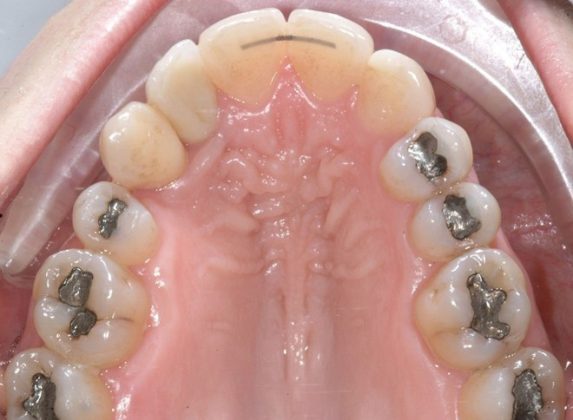

Al termine del trattamento ortodontico, che ha richiesto 24 mesi di terapia, è stata applicata una contenzione fissa3 all’arcata inferiore mediante filo multi-intrecciato coassiale .0195” esteso da 4.4 a 3.5 al fine non solo di stabilizzare il risultato sia sul piano orizzontale sia verticale, ma soprattutto per prevenire adeguatamente l’affollamento dentale terziario (Figure 9a-e).

All’arcata superiore è stato mantenuto il pontic in composito in sede 1.2, poiché la paziente, per esigenze personali, aveva preferito rimandare a un tempo successivo la sostituzione implantare di 1.2 agenesico, così come la coronoplastica definitiva di 2.3.

Dopo tre anni dal termine del trattamento ortodontico, la paziente ha richiesto di finalizzare il suo caso; è dunque stata effettuata la sostituzione implanto-protesica dell’elemento 1.2, senza necessità di ulteriori rifiniture ortodontiche, avendo mantenuto, grazie al pontic in composito, un ottimo parallelismo radicolare tra 1.1 e 1.3.

È stata eseguita contestuale terapia rigenerativa, per ottimizzare qualità e quantità dei tessuti nel sito implantare. Come si rileva dalle immagini di follow up, dopo la fase implanto-protesica superiore, è stata applicata anche una parziale contenzione fissa tra gli incisivi centrali superiori e il risultato ortodontico si è mantenuto stabile nel tempo (Figure 10 a-e).